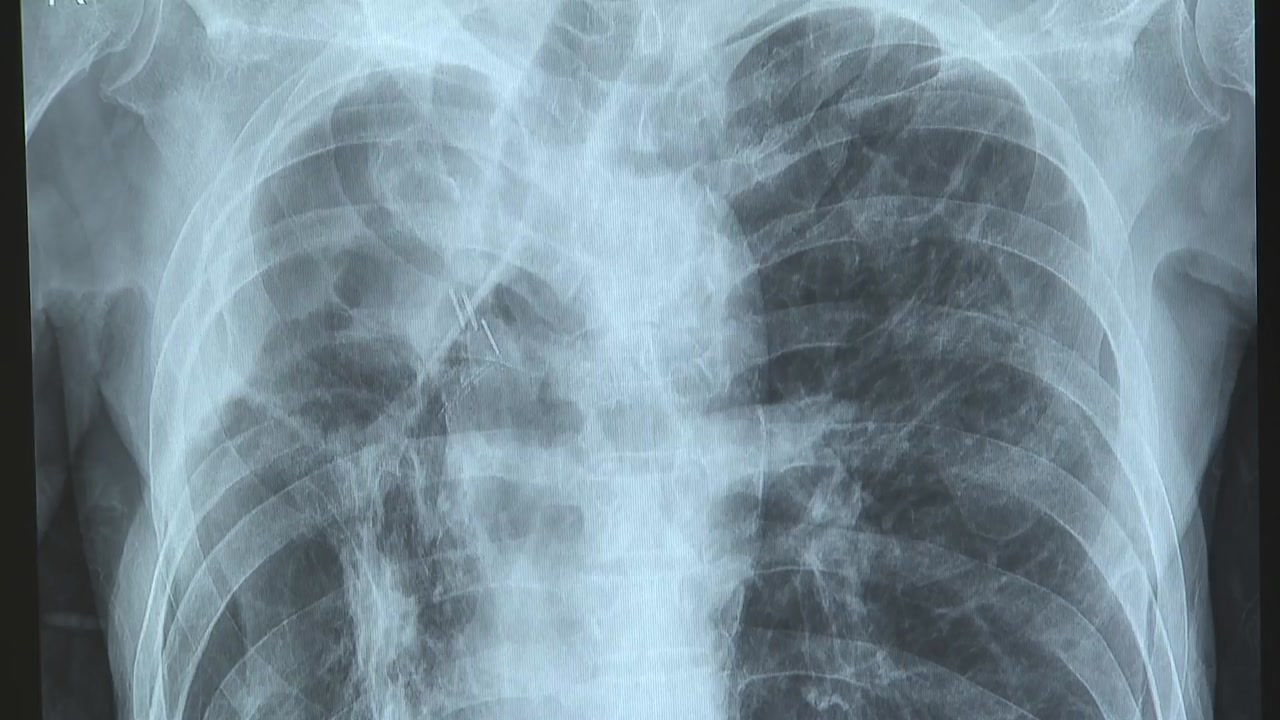

만성폐쇄성폐질환, COPD는 기도와 폐포에 이상이 생기면서 폐 안으로 들어온 공기가 밖으로 빠져나가지 못하게 되는 병을 말합니다.